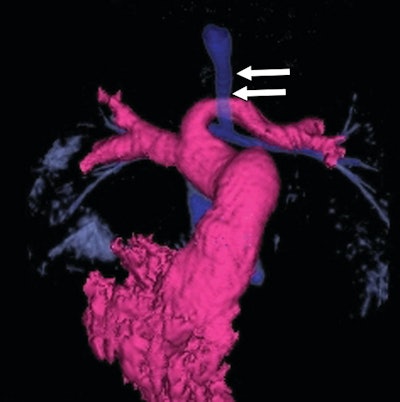

- On all radiographs of the pediatric chest, radiologists should assess the caliber and position of the trachea and the laterality of the aortic arch. These can provide the first clues of the presence of a vascular anomaly.